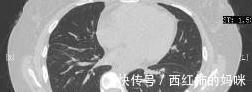

01病例一:23岁女性,确诊肺癌晚期1+年。

去年,这位患者在受凉后出现咳嗽、咳痰,到医院进行治疗,查胸水脱落细胞学检查提示:查见异型细胞,疑为腺癌细胞,结合免疫组化,查见腺癌细胞,倾向于肺来源。PET—CT检查结果提示:颈胸腹部淋巴结、双肺、右侧胸膜及全身多处骨骼糖代谢增高,多系恶性肿瘤,考虑肺癌伴其余部位转移可能性大。最后得到的病理诊断是肺癌伴全身多处转移。